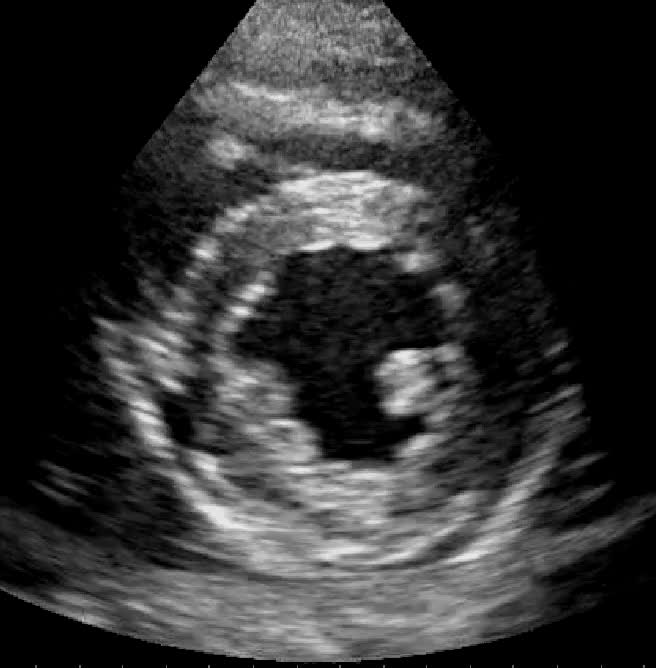

Visualizzazione 3D dell'auricola sinistra, a destra si visualizza parte della parete laterale con l'ostio dell'auricola, a sinistra si visualizza la parete inferiore e si intravede il lembo anteriore della valvola mitrale. Immagine ottenuta mediante Zoom 3D in proiezione medio esofagea 2 camere.